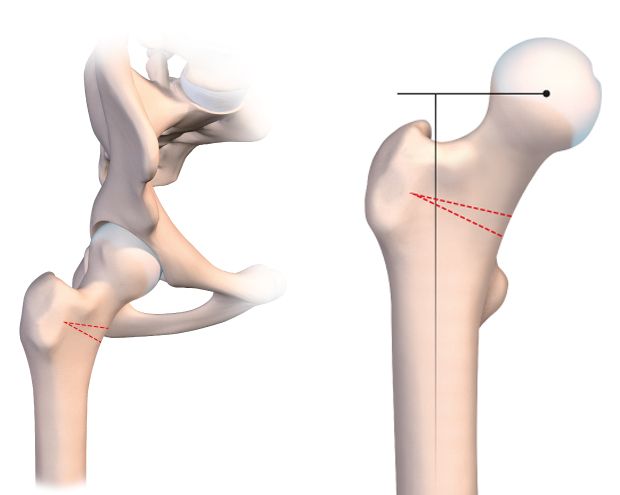

The osteotomy line is usually situated at the base of the neck. It should be as horizontal as possible to improve postoperative stability and avoid any slipping or instability (Fig. 2a).

For a varus-producing osteotomy, a wedge can be removed from the medial base, matching the desired angle of correction. The higher the line, the more accurate the wedge calculations must be because it is all to easy to exaggerate the valgus correction by having the line too close to the neck. The preoperative planning must be just as meticulous as for the traditional technique. We use new computer tools to simplify and even simulate this type of surgery.